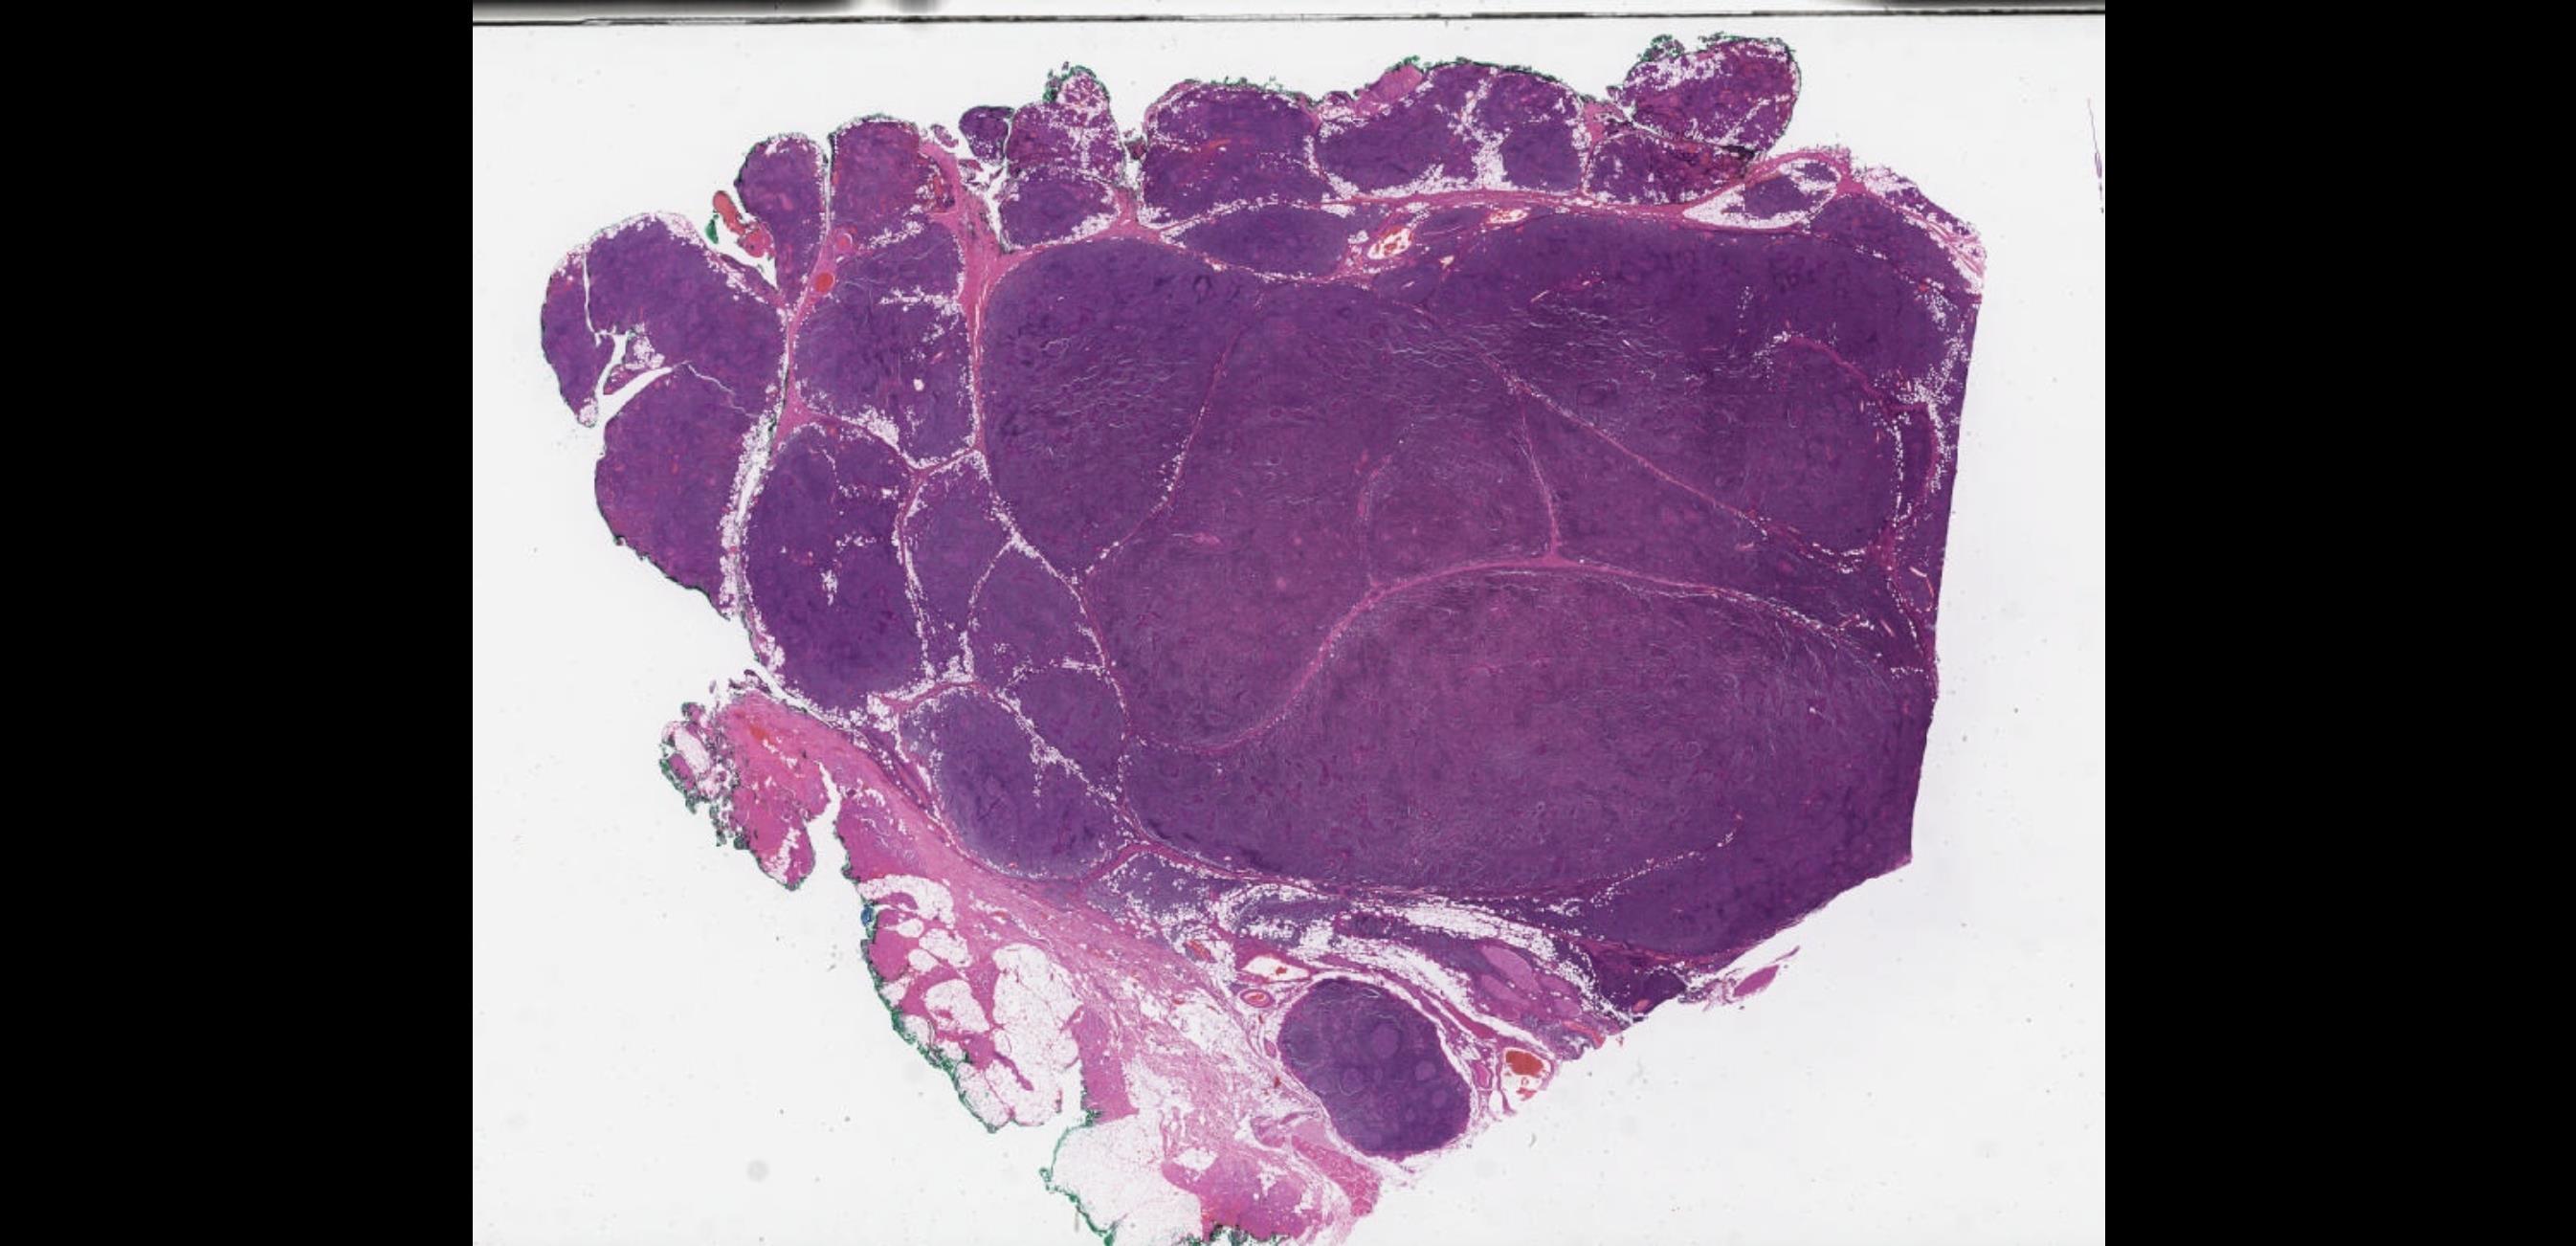

Male 64 years, Left parotid gland mass.

??

Case 19 Diagnosis

Extranodal marginal zone lymphoma (MALT)

•H&N 2nd most common site after GI tract •Small lymphocytes and marginal zone cells •Monocytoid cells with abundant pale cytoplasm are sometimes present •Remnants of reactive follicles are

sometimes with follicular colonization.

formed lymphoepithelial lesions

common,

Well-

• Positive for CD20, CD22, PAX5), usually IgM, occasionally IgG or IgA, and rarely IgD, CD43 or TBX21 (T-bet)

• Negative for CD5, CD10, BCL6, CD23, cyclin D1, SOX11, and EBV

• Immunoglobulin light chain monotypia of B cells or plasma cells